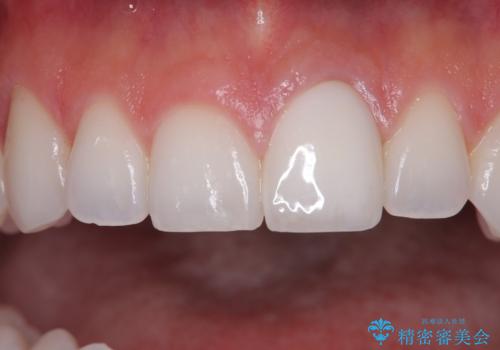

ぶつけて変色した前歯 オールセラミッククラウン治療

- 以前ぶつけて神経を取り除いてから、徐々に変色してきた前歯が気になるとのことで来院された患者様です。

神経を取り除いた歯の変色はホワイトニングでは十分に改善できないため、オールセラミッククラウンにて補綴治療を行うこととしました。

定期的にホワイトニングをされていることや、前歯の歯列が左右非対称であることから、色合いや形態の修正が多くなることが予想されたため、オーダーメイドタイプのグレードを選択していただき、治療を進めて行くこととしました。

予想通り色と形の修正が多く必要となりましたが、最終的には納得のいく仕上がりとなりました。